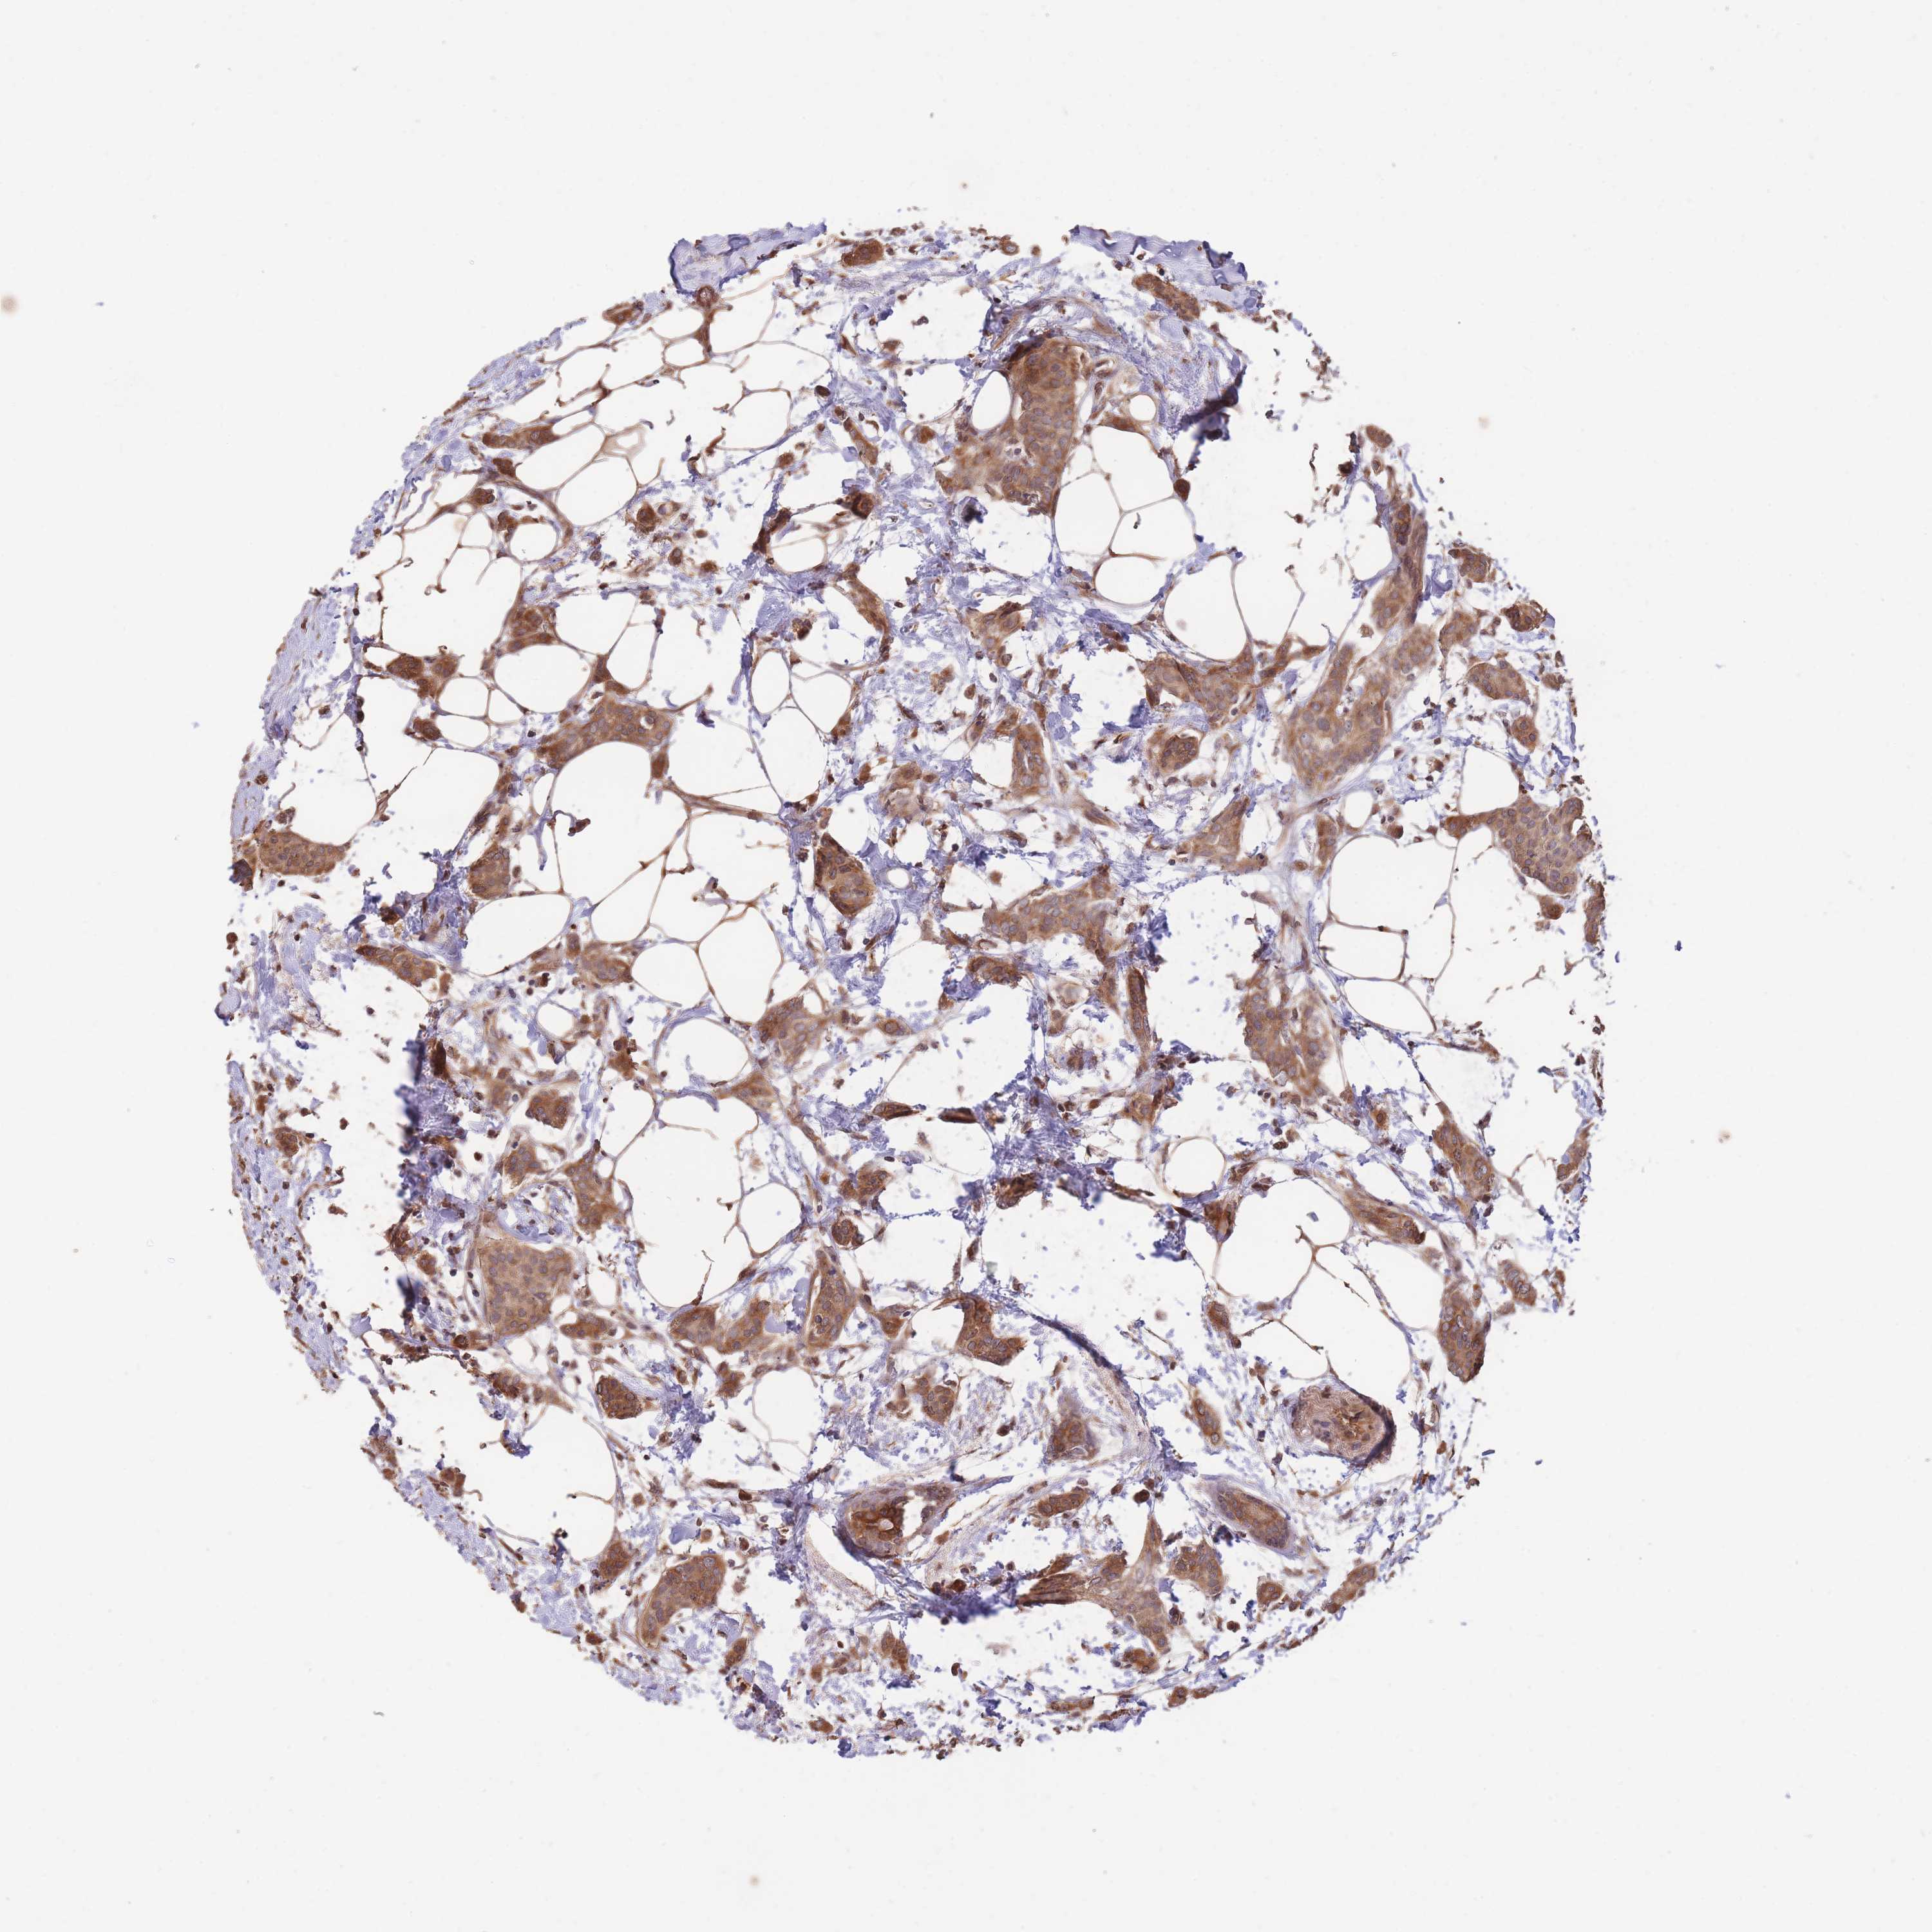

CANCER BREAST CANCER Show tissue menu

BRCA TCGA BRCA VALIDATION PROTEIN EXPRESSION